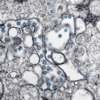

More than a dozen Md. biotech companies are working on new COVID-19 vaccines, tests

Novavax and Emergent Biosolutions are not the only Maryland companies developing COVID-19 countermeasures. More than 15 local companies will meet virtually Friday to share their efforts.